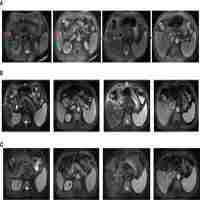

| Abstract | Pulmonary sarcomatoid carcinoma (PSC) is a rare subtype of non-small cell lung cancer with high malignancy and poor prognosis. Chemotherapy or radiotherapy do not usually provide satisfactory results in patients with PSC, especially in those with advanced-stage cancer. Targeted therapy and immunotherapy are more precise therapies that may be effective in the treatment of PSC; however, further research is needed. Here, we present a case of stage III PSC with obstructive atelectasis, which is more challenging and hinders treatment. Treatment with the PD-1 inhibitor camrelizumab and transbronchial cryoablation showed significant clinical efficacy. This type of combined treatment has not been reported previously for PSC. Thus, this case may provide a valuable reference for future clinical practice and research. |